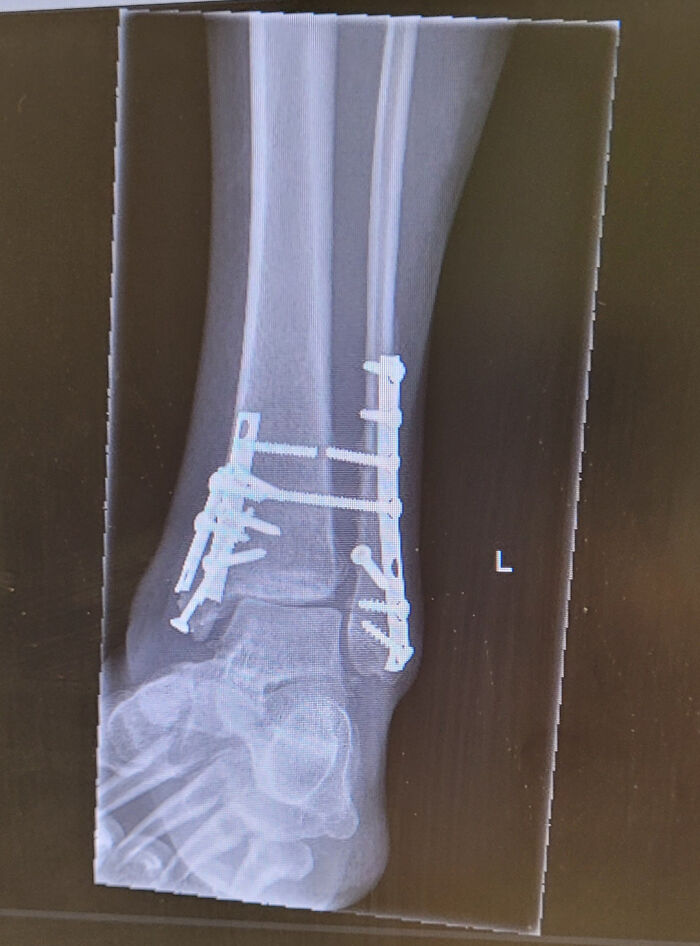

Ankle Injury, 15 Week Update

X-ray of a human ankle with metal screws and plates showing fascinating and wild things that can happen to the human body.

The news wasn’t the best. The doctor said the bones are healing fine, but they seem to be moving apart. You can see the top syndesmotic screw is already broken- however, he thinks my issue is the ligament(s). So now I wait for a CT scan.

redbycyrenz Report